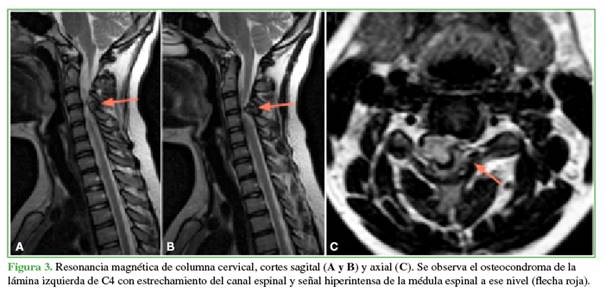

Tras ser derivada al Servicio de Patología de Columna Vertebral debido a un hallazgo incidental de osteocondroma cervical en una tomografía computarizada (TC) de rutina, en mayo de 2020, la paciente no tenía síntomas cervicales. El examen neurológico reveló hallazgos normales, con reflejos presentes y signos negativos de Hoffman, clonus y Babinski. En la TC de columna cervical, se visualizó un osteocondroma ubicado en la lámina izquierda de C4, con extensión hacia el canal espinal (Figura 2). Además, se observó un osteocondroma pediculado en la pared posterior de T1, también con extensión hacia el canal espinal, junto con un osteocondroma en el proceso espinoso de C2. La resonancia magnética (RM) subsecuente de columna cervical confirmó la presencia del osteocondroma en la lámina izquierda de C4, que causaba una reducción en el diámetro del canal y tenía una señal hiperintensa en las secuencias en T2 (Figura 3).

Los otros dos osteocondromas espinales detectados en la TC no provocaban un compromiso medular según la RM. Los potenciales evocados subsensitivos de las cuatro extremidades indicaron una disminución en la amplitud. Ante este cuadro clínico, se decidió someterla a una descompresión cervical posterior y la resección del arco posterior de C4 sin instrumentación (Figura 4).